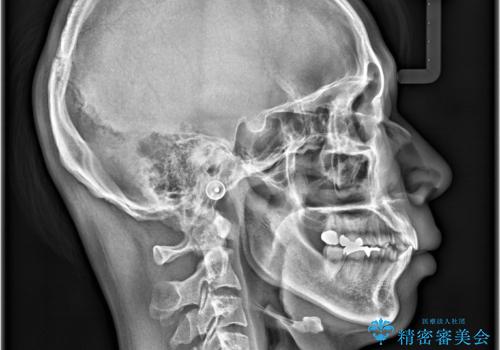

- 前歯の隙間と歯のデコボコを主訴にご来院された患者様です。

加えて、上下の奥歯が全く咬み合わないシザーズバイトの状態も認められました。

矯正検査の結果、非抜歯でインビザラインによる治療が可能と判断し、治療を行いました。